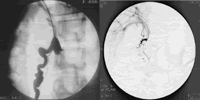

入院后予止血、营养支持等保守治疗,患者排少量黑便。在内镜检查后,立即同时股动脉、股静脉插管行腹腔动、静脉造影和经皮经肝门静脉造影,发现SMV在右下腹区明显迂曲、增粗(图4、5),静脉期见与下腔静脉相通,用栓塞剂及弹簧圈栓塞后重复造影示增粗静脉支消失(图6)。术后曾出现右侧血性胸腔积液,经抽取胸腔积液、抗感染等治疗后好转。3周后复查上消化道造影,未见十二指肠充盈缺损,考虑曲张静脉已栓塞完全。术后复查Hb (92~112) g/L,PLT(56~70)×109/L;便潜血(-)。出院随诊。

图5 经皮经肝门静脉造影见异位曲张静脉

图6 栓堵后曲张静脉消失, http://www.100md.com